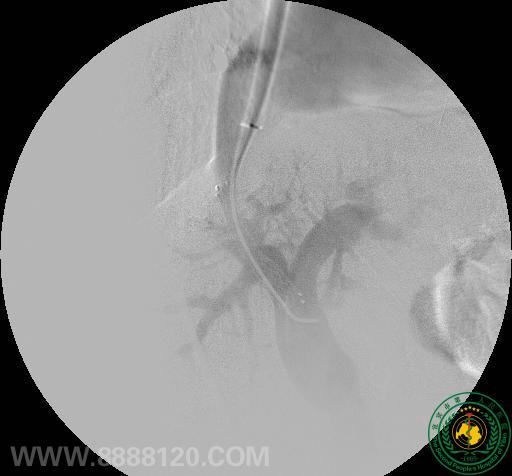

2012年11月15日,放射介入科成功开展了一例经颈静脉肝内门体支架分流术(TIPS),这是宜宾市第一例经颈静脉肝内门体支架分流术(TIPS)。

患者为60岁老年男性,诊断肝硬化,反复腹胀,顽固性腹水。经消化科陈扬主任医师、介入科曹跃勇主任医生、朱军主治医生及黄勇医师反复研究病情,决定对其实施TIPS手术。术中经肝右静脉成功穿刺门静脉右支,并顺利行分流道球囊扩张,再于适当位置释放覆膜支架一枚。术后造影见门静脉内血流经分流道进入肝静脉,并由下腔静脉回到右心房。术中及术后患者未见特殊不适。